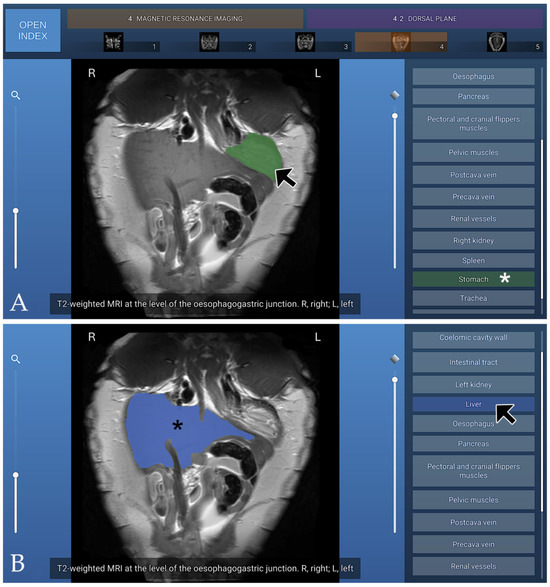

Anatomic Interactive Atlas of the Loggerhead Sea Turtle (Caretta caretta) Coelomic Cavity

The coelomic cavity of sea turtles is affected by congenital, developmental, traumatic, infectious, and organ- or system-specific disorders, making accurate anatomical knowledge essential for veterinary practice. This study presents an open-access, interactive two-dimensional (2D) anatomical atlas of the coelomic cavity of the loggerhead [...] Read more.

The coelomic cavity of sea turtles is affected by congenital, developmental, traumatic, infectious, and organ- or system-specific disorders, making accurate anatomical knowledge essential for veterinary practice. This study presents an open-access, interactive two-dimensional (2D) anatomical atlas of the coelomic cavity of the loggerhead sea turtle (Caretta caretta), developed using images obtained from osteology, gross anatomical dissections, computed tomography (CT), and magnetic resonance imaging (MRI). The atlas comprises six osteology images, sixteen anatomical dissection images, eight transverse CT images acquired using bone and soft-tissue windows, six three-dimensional (3D) volume-rendered CT images, and fourteen MRI images (four transverse, five dorsal, and five sagittal), all provided in PNG format. Relevant anatomical structures were segmented and colour-coded for each figure using manual layer-based segmentation software. The Unity 3D platform was employed for image visualisation and assessment, supporting the development of interactive two-dimensional content. This atlas serves as a useful interactive tool for anatomical learning and clinical reference for professionals and students engaged in the conservation of loggerhead sea turtles. Full article

Show Figures

Figure 1